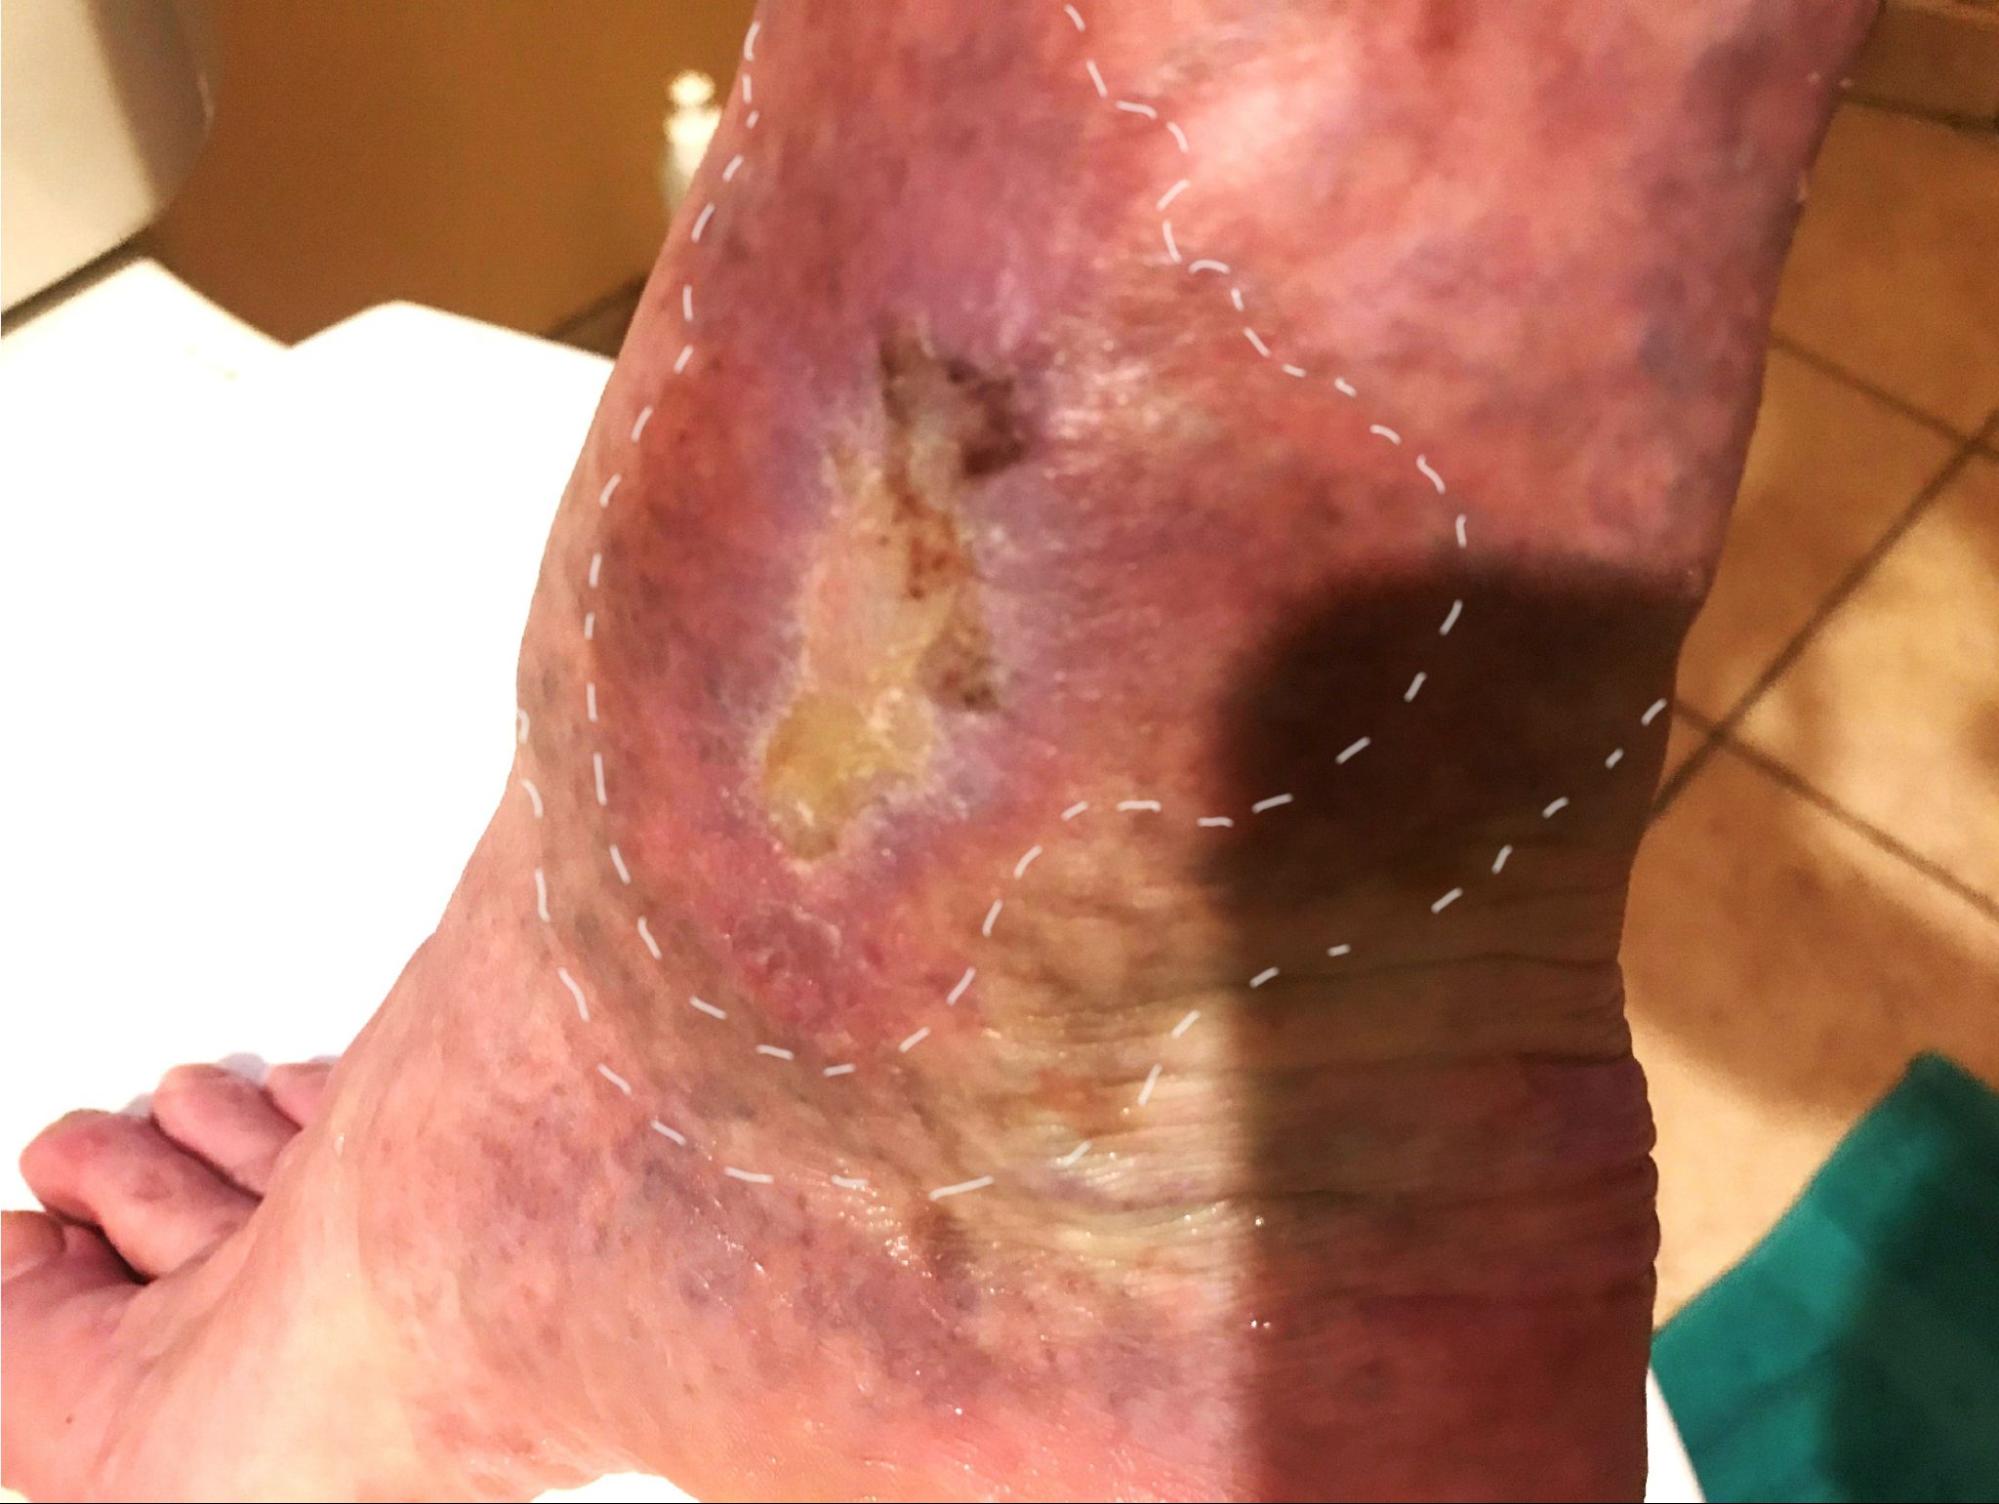

Both lower legs were visually examined and palpated. Black and dark blue varicose veins were prominent on the medial aspect of the right lower leg from the knee to the ankle, mainly along the Spleen and Kidney channels. A wound with a thin scab and no signs of infection showed on the right shin above the medial malleolus. The wound measured approximately 0.5 inches wide and 1.5 inches long. The scab was thin, smooth, and pale yellow. In addition, there was an area of brown and black hemosiderin staining approximately four inches wide and eight inches long. Edema was visible around the right medial malleolus and the distal margins of the hemosiderin staining (see Figure 1). The left lower leg was clear of lesions.

According to Bowers and Franco, there are four stages of wound healing. Stage one is called the hemostasis or coagulation stage, where vasoconstriction and clotting occur, causing the wound to stop bleeding. The second stage is the inflammation stage, in which the release of cytokines and growth factor leads to vasodilation. In turn, this allows for an immune response and phagocytosis at the wound site. As a result, the area becomes red, swollen, warm, and painful—all classic signs of inflammation. This stage can be seen in Figure 1. Stage three is the proliferation stage, in which granulation and epithelialization allow the wound to close. This is when new blood vessels proliferate and enable blood flow to the area. Figure 2 may show this stage of wound healing in the patient. The final stage is called the maturation or remodeling stage. Collagen creates a scar at the site of the wound. Over time, scar strength will increase up to 80% of the original tissue strength (Bowers & Franco, 2020). Achieving this final stage enabled GM to wear his work boots for extended periods without tissue breakdown.

Using the location, depth, and appearance of the wound, specifically the signs of edema and hemosiderin staining on GM’s leg, he was diagnosed as having a venous wound type. This mandated increased precautions for safe acupuncture practice. The hemosiderin staining is seen clearly in Figures 1 and 2. Figure 4 shows the texture of the compression sock due to localized edema. Figure 4 shows the reduction of inflammation and hemosiderin staining since the first treatment.